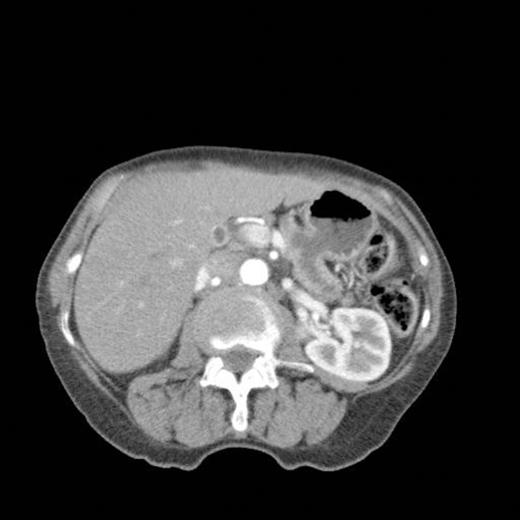

CT scan done at 10 years after initial diagnosis as part of routine surveillance revealed gross dilatation of main pancreatic duct to 10 mm along with a widely patent communication between the pancreatic duct and the stomach raising the possibility of a spontaneous gastro-pancreatic fistula measuring up to 19 mm associated with layering of mucin within the stomach. (Fig 3). The pancreas did not reveal any mass lesion and was globally atrophic. An upper GI endsocopy was done and this revealed a little crater with mucus plug in the body of the stomach along the lesser curve representing the opening of the gastropancreatic fistula. Biopsies taken around the fistula revealed non-specific inflammation. On clinic review, the patient complained of increased frequency of bowel habits, which was thought to be due to intestinal hurry caused by the fistula. This responded well to increased dose of creon.